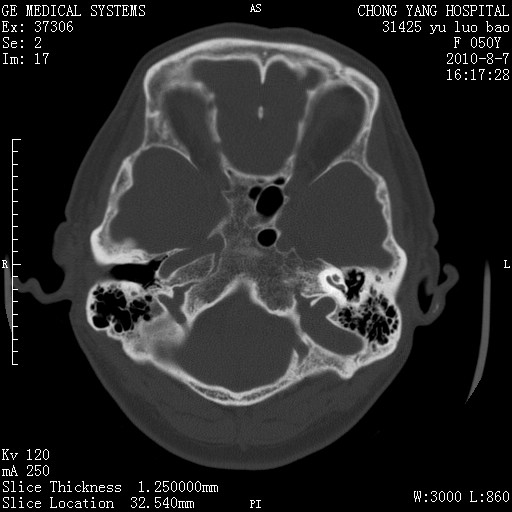

标题: CT28285:听力下降一年,头昏。

右侧桥小脑角区占位--听神经瘤,建议增强或mri检查。

右侧桥小脑角去等密度占位,右侧内听道扩大、骨质吸收,考虑:右侧听神经瘤,建议增强检查。

右侧内听道扩大、骨质吸收,中脑受压左移,考虑:右侧听神经瘤,建议增强检查。支持!

骨窗示右侧内听道扩大,考虑右侧听神经瘤。

右侧桥小脑角区等密度占位,内耳道扩大,听神经瘤